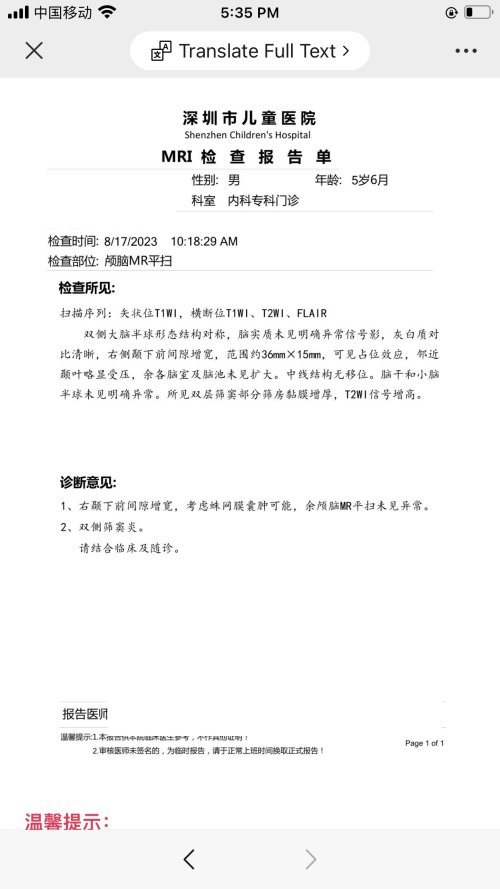

反馈下情况,孩子在国内的医院已经进行过一轮全面检测,没发现什么问题,但是现象是存在的。医生也没什么办法。医生说核磁共振和脑电图没问题,我们也不是很看得懂,各位如果懂的,请指点一下。另外进行了部分基因检测,没发现异常。下一步,我们国庆后打算去更权威的医院去碰碰运气。谢谢各位!

513.6 KB 查看: 103

532.8 KB 查看: 142

551 KB 查看: 132

526.8 KB 查看: 133

510 KB 查看: 103

506.4 KB 查看: 124

495.7 KB 查看: 165